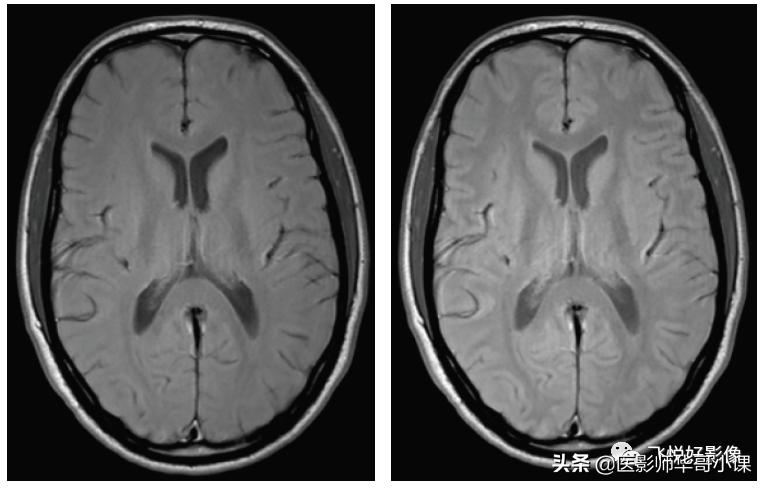

图4,TSE PD加权图像。横断面脑实质PD加权图像,左图TR=1500ms,TE=20ms,右图TR=2000ms,TE=20ms。PD加权图像主要反映组织的质子密度,在长TR时间条件上,纵向弛豫已完全恢复,在短TE时间条件下,横向弛豫衰减不明显,因而在长TR、短TE时,图像信号强度反映的是组织质子密度。PD加权图像解剖结构的显示不如T1加权图像,脑灰质相对于脑白质相对呈中高信号,脑脊液信号与脑灰质类似,脂肪组织仍显示为高信号,而骨结构、空气等在磁共振中不产生信号。(图像源自飞利浦磁共振系统)